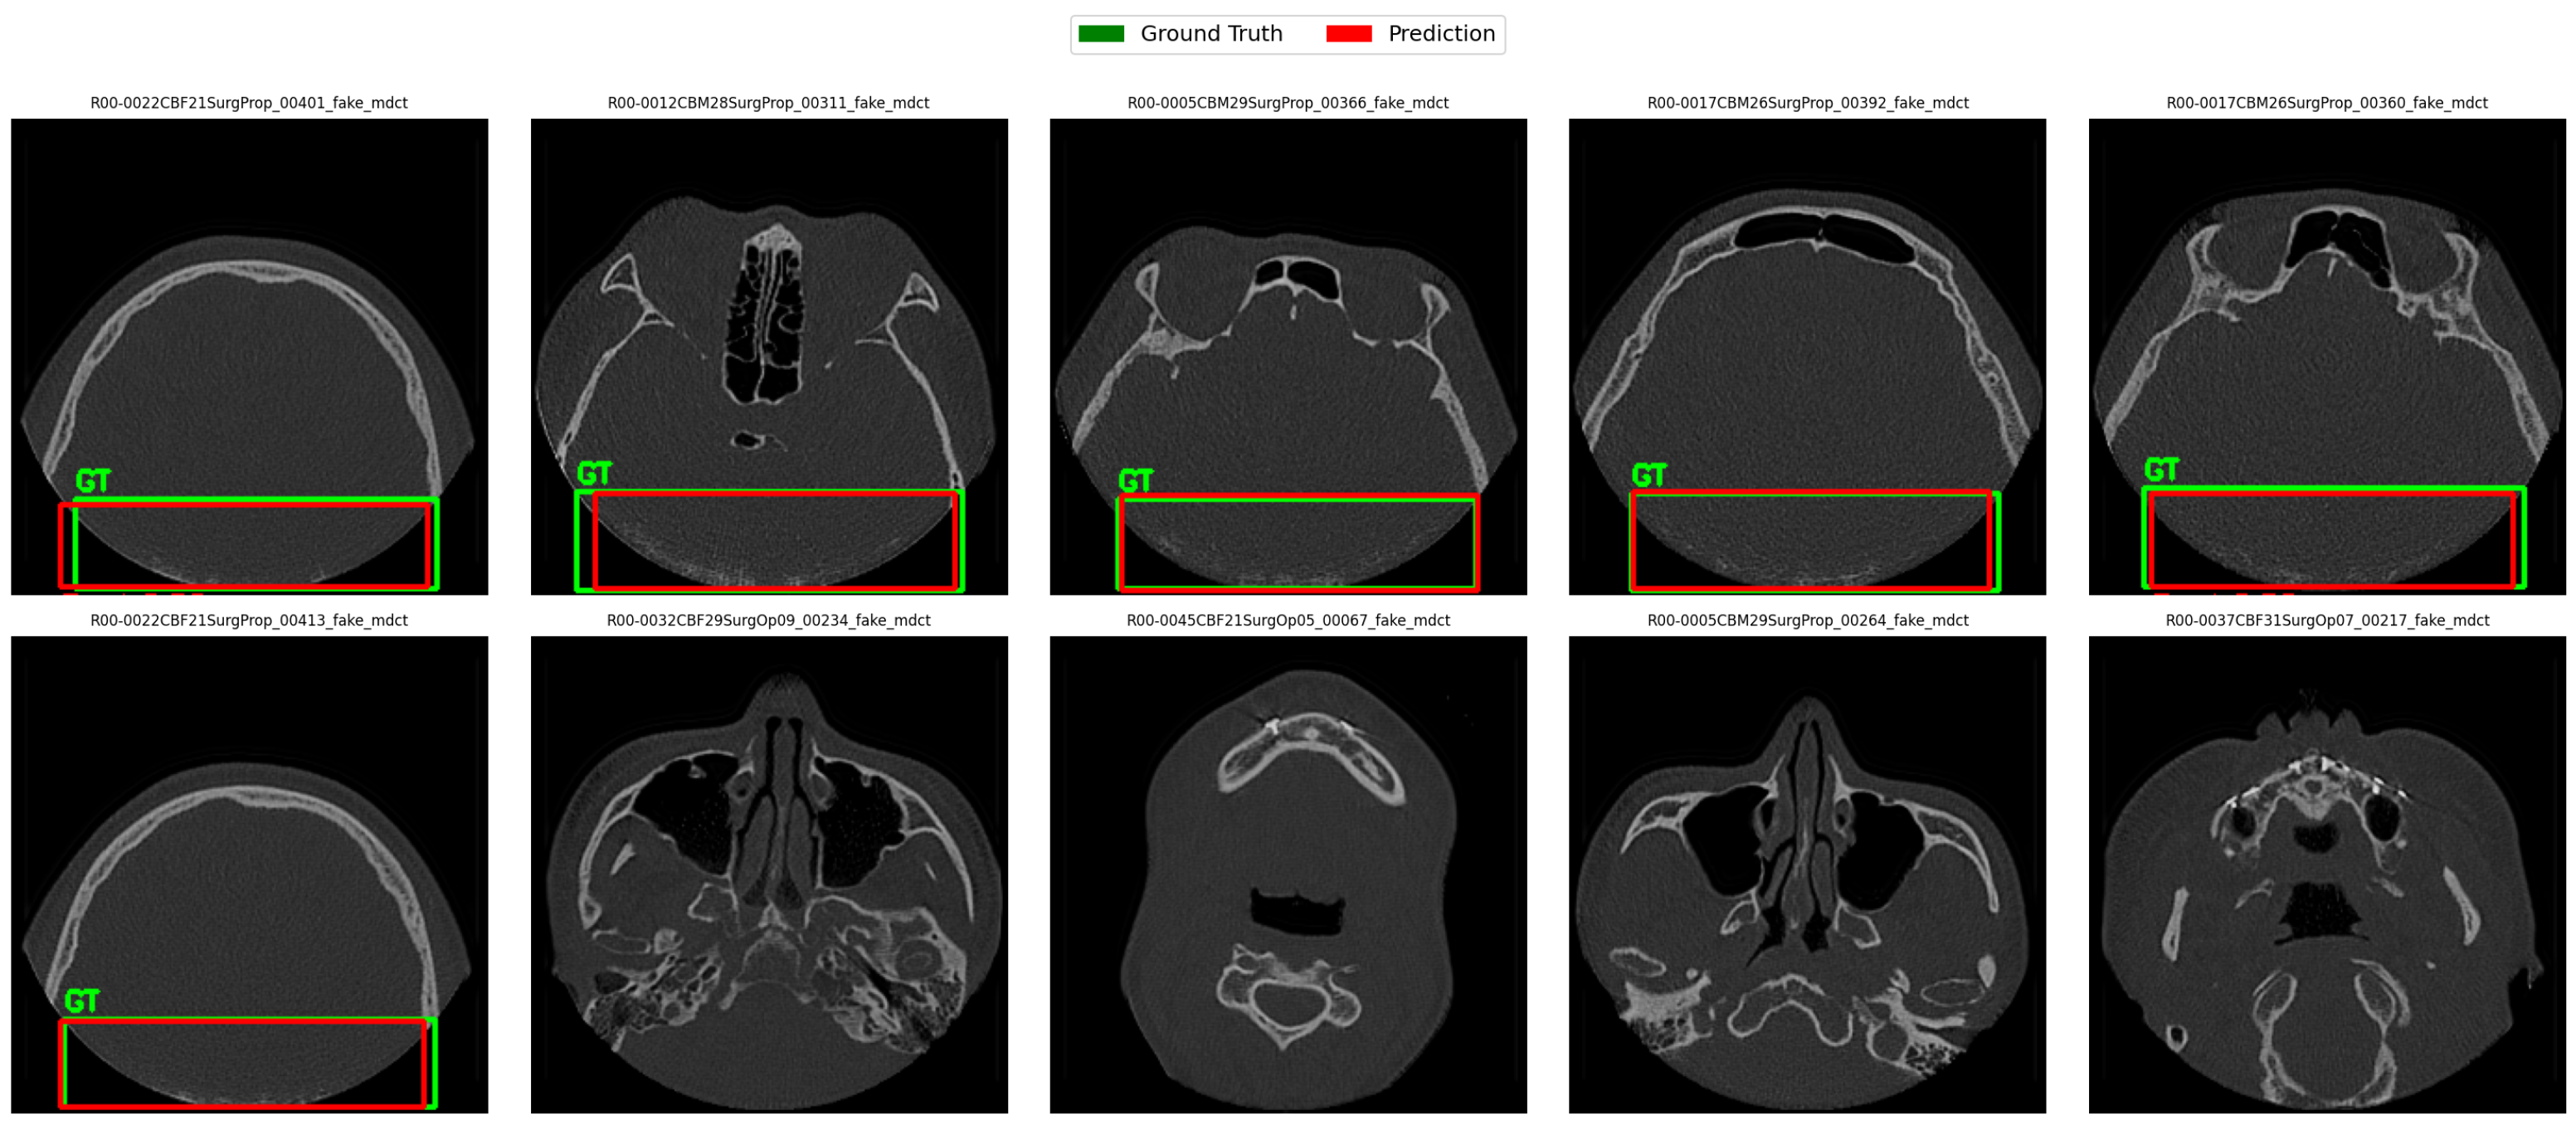

4.4. Qualitative Results

4.8. YOLO Detector Performance